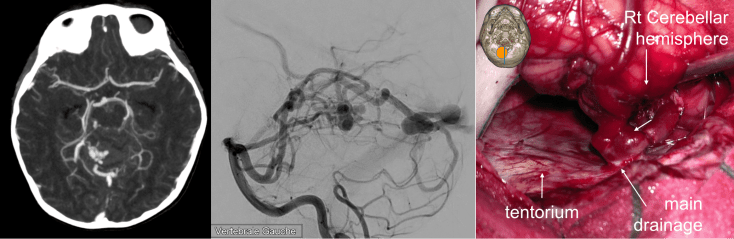

MAV cérébelleuse

les MAV cérébelleuses sont particulièrement dangereuses et sont au premier rang de la mortalité par saignement de MAV.

il s’agit donc d’une indication de chirurgie urgente, sans attendre la dégradation neurologique qui est brutale.

l’imagerie injectée (angioscanner ou comme ici ARM) permet de localiser le nidus par rapport à l’hématome.

opératoirement, devant un cervelet tendu, il est souvent illusoire de tenter de contrôler les pédicules avant d’évacuer l’hématome, cette évacuation est alors le premier temps de l’abord du nidus, qui est ensuite contrôlé en isolant progressivement les afférences artérielles à sa périphérie et en terminant par le drainage veineux.

ici, le saignement opératoire est plus lié aux veines cortico-durales et aux sinus veineux duraux sous pression qu’à la MAV elle-même.

dans certains cas, où les pédicules sont volumineux et le drainage peut être contourné, on parvient à réaliser un contrôle exsangue de la malformation.